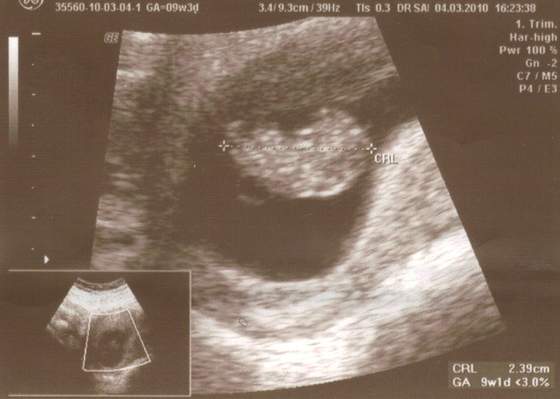

Oj widze ze dla moriam i joanna0984 dzieciaczki sie pleckami odwrucily ;-) Slodziaki!